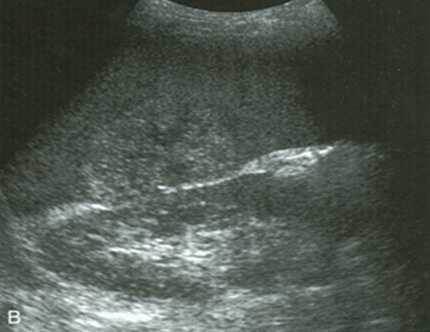

- Кисты селезенки. УЗИ сканограмма